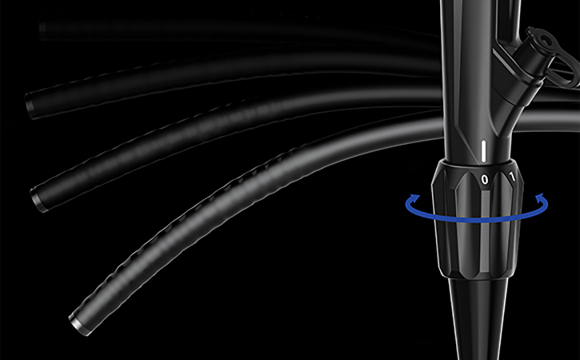

Синхронизация передачи усилияИнерционная конструкция во вводной части колоноскопа. Во время обследования он может передавать толкающие, вытягивающие и вращательные усилия, прилагаемые оператором к рукоятке, на дистальный конец колоноскопа, способствуя лучшему введению в цекум. Регулируемая жесткостьВводная трубка колоноскопа имеет функцию многоуровневой регулировки мягкости и жесткости.Вращая регулировочное кольцо, можно изменять мягкость и твердость вводимой части в соответствии с требованиями эндоскопии различных отделов толстой кишки, как того требуют врачи-клиницисты.

Регулируемая жесткостьВводная трубка колоноскопа имеет функцию многоуровневой регулировки мягкости и жесткости.Вращая регулировочное кольцо, можно изменять мягкость и твердость вводимой части в соответствии с требованиями эндоскопии различных отделов толстой кишки, как того требуют врачи-клиницисты. Эластичный изгибВо время эндоскопических процедур он может адаптироваться к различным изгибам толстой кишки. Способен саморегулироваться и поворачивать корпус эндоскопа к просвету в таких областях, как изгиб селезенки и печеночный изгиб, что уменьшает необходимость манипуляций с эндоскопом и повышает комфорт пациента.

Регулируемая жесткость. Колоноскоп оснащён многоуровневой системой регулировки жёсткости вводной трубки. С помощью кольца на корпусе можно плавно изменить степень жёсткости — от более гибкой до более жёсткой. Это позволяет врачу адаптировать поведение эндоскопа под конкретную анатомию пациента и тип вмешательства: при прохождении изгибов — использовать мягкий режим, при необходимости продвижения по прямому участку — увеличить жёсткость для лучшей управляемости.